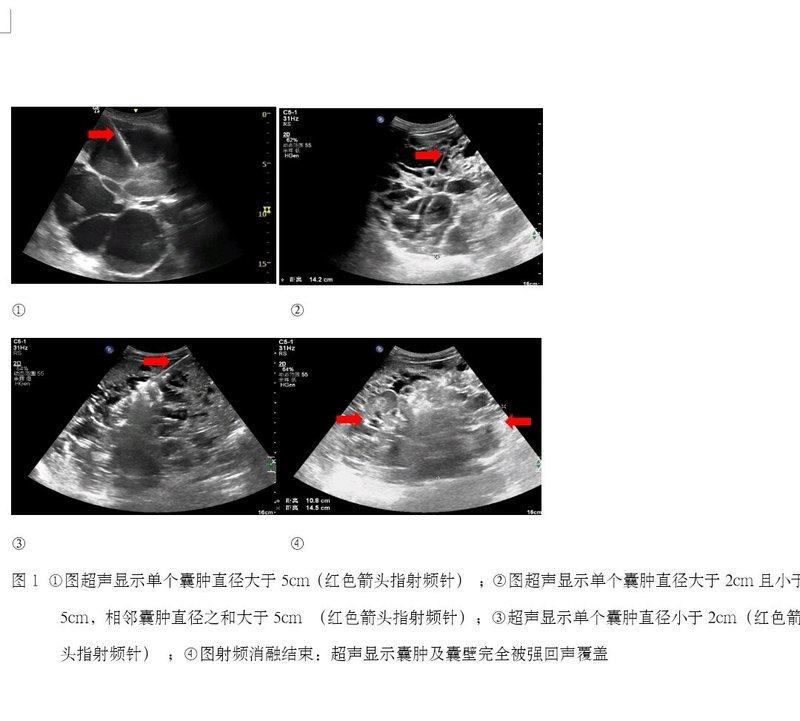

經(jīng)皮射頻消融治療多囊肝病的初步臨床研究

多囊肝?。ˋPLD)是一種遺傳性疾病,以肝臟多發(fā)散在的囊腫為特征,常常伴有多囊腎。早期無(wú)明顯臨床癥狀,隨著囊腫進(jìn)展,肝臟體積增大,可出現(xiàn)腹痛,腹脹、惡心、嘔吐等臨床表現(xiàn)[1,2]。目前,多囊肝病的臨床治療復(fù)發(fā)率高,并發(fā)癥多,效果不甚理想,而且臨床上沒(méi)有統(tǒng)一的治療方法[3]。我科在國(guó)際上首次對(duì)多囊肝病患者實(shí)施了超聲引導(dǎo)下射頻消融治療,已成功完成13例,充分證明了經(jīng)皮射頻消融治療多囊肝病的有效性及安全性。 1資料與方法 一般資料 本研究回顧性分析2018年1月-2019年12月在我科接受射頻消融治療的14例多囊肝病患者,其中,男性4例,女性10例,年齡35-64(51±8)歲。14例多囊肝患者的臨床資料如下(見(jiàn)表1)。14例患者均經(jīng)肝臟增強(qiáng)CT或增強(qiáng)MRI確診為多囊肝病,且引起臨床癥狀,如腹脹、腹部隱痛等。肝功能Child-Pugh分級(jí)A級(jí)。凝血功能正常,無(wú)其他全身性感染等禁忌癥。 1.2 儀器與設(shè)備 采用綿陽(yáng)立德公司生產(chǎn)的多極射頻消融系統(tǒng)(冷循環(huán)),型號(hào)為L(zhǎng)DRF-120S。超聲設(shè)備為PHILIPS EP IQ7,變頻探頭型號(hào)為C5-1,探頭頻率為1~5MHZ,用于超聲引導(dǎo)治療。 1.3 方法 術(shù)前完善血常規(guī)、凝血功能、肝腎功能、傳染病、心肺功能等檢查。術(shù)前禁食水8 h,酌情行腸道準(zhǔn)備;術(shù)前行超聲檢查,評(píng)估消融范圍及擬定消融進(jìn)針?lè)桨浮J中g(shù)操作:患者平臥位,常規(guī)消毒、鋪無(wú)菌單,全麻(為了盡可能多的消融囊腫,延長(zhǎng)手術(shù)時(shí)間),超聲引導(dǎo)下先行17G消融電極(帶抽吸側(cè)孔)進(jìn)入囊腫內(nèi),待抽凈囊內(nèi)液體后,啟動(dòng)消融設(shè)備,起始功率設(shè)置為150W,進(jìn)行囊壁RFA治療,至囊壁完全被強(qiáng)回聲覆蓋,消融結(jié)束。治療方案(圖1):a.對(duì)于單個(gè)囊腫直徑>5cm或者單個(gè)囊腫2cm<D<5cm且相鄰囊腫直徑之和>5cm,先行射頻電極依次進(jìn)入囊內(nèi),抽凈囊液,待囊壁皺縮至附著于電極,然后啟動(dòng)消融,對(duì)囊腫回縮區(qū)進(jìn)行消融,至囊壁被強(qiáng)回聲覆蓋,消融結(jié)束。b.對(duì)于囊腫直徑<2cm,無(wú)需抽液,射頻電極直接進(jìn)入囊腫聚集區(qū),啟動(dòng)消融,至囊腫及囊壁被強(qiáng)回聲覆蓋,消融結(jié)束。若有足夠正常肝實(shí)質(zhì)代償情況下,盡可能多的消融囊腫。若沒(méi)有足夠正常肝實(shí)質(zhì)代償,對(duì)于此類(lèi)小囊腫可達(dá)到a中標(biāo)準(zhǔn)時(shí)再做處理。 1.4 療效評(píng)價(jià) 觀察術(shù)后并發(fā)癥(出血、膽瘺、腹水等);平均住院時(shí)間;比較射頻消融治療前與治療后12個(gè)月患者肝內(nèi)囊腫總體積(使用CT機(jī)的 Volume測(cè)量軟件對(duì)囊腫體積進(jìn)行測(cè)量并記錄);檢測(cè)治療前與治療后1周肝功能(ALT,AST,TBIL),評(píng)價(jià)射頻消融治療對(duì)肝功能的影響。 1.5 統(tǒng)計(jì)學(xué)分析 應(yīng)用SPSS 21.0 軟件進(jìn)行統(tǒng)計(jì)分析,計(jì)量單位以均數(shù)±標(biāo)準(zhǔn)差((X±S)表示,比較射頻消融治療前與治療后12個(gè)月肝內(nèi)囊腫總體積,射頻消融治療前與治療后1周肝功能改變,采用配對(duì)t檢驗(yàn),P<0.05為差異有統(tǒng)計(jì)學(xué)意義。 2 結(jié)果 2.1 射頻消融后并發(fā)癥等情況 1例患者因術(shù)中出血,終止治療。余13例多囊肝患者射頻消融治療后即刻囊腔消失、肝內(nèi)囊腫總體積縮小。術(shù)后腹脹較術(shù)前明顯好轉(zhuǎn)。術(shù)后第1d,3例患者出現(xiàn)上腹部輕度疼痛,疼痛評(píng)分4級(jí)(考慮術(shù)后反應(yīng)),給予保肝、抗炎等處理,腹部疼痛較前好轉(zhuǎn),2例患者自訴夜間惡心嘔吐,無(wú)其他不適,給予患者營(yíng)養(yǎng)支持、補(bǔ)液等對(duì)癥處理,癥狀好轉(zhuǎn),余8例患者無(wú)其他不適。術(shù)后1周,癥狀明顯緩解率為92.31%(12/13)?;颊咂骄≡海?±2)d。術(shù)后12個(gè)月,1例患者因肝內(nèi)最大囊腫囊壁未消融完全,囊腫復(fù)發(fā)。 2.2 比較射頻消融治療前與治療后12個(gè)月患者肝內(nèi)囊腫總體積 射頻消融治療12個(gè)月后肝內(nèi)囊腫總體積與治療前相比,治療前的囊腫總體積為(2573.35~5960.11)cm3,平均值為(4068.91±1145.11)cm3 ,治療后12個(gè)月為(1305.70~2862.23)cm3,平均值為(2027.17±584.70)cm3,采用配對(duì)t檢驗(yàn),t=9.259, P<0.05,差異有統(tǒng)計(jì)學(xué)意義(見(jiàn)表 2)。13例肝內(nèi)囊腫總體積縮小率26.33%~63.03%,平均(49.60±10.04)%。 2.3檢測(cè)射頻消融治療前與治療后1周肝功能(ALT,AST,TBIL),評(píng)價(jià)射頻消融治療對(duì)肝功能的影響 13例多囊肝患者射頻消融治療前與治療后1周的 ALT、AST、TBIL均無(wú)顯著差異(P>0.05)(見(jiàn)表3),射頻消融對(duì)患者肝功能影響較小。 3 討論 臨床上治療多囊肝病的常用方法有超聲引導(dǎo)下囊腫穿刺抽液及硬化治療,腹腔鏡下或開(kāi)腹開(kāi)窗去頂術(shù),肝部分切除術(shù),肝切除聯(lián)合囊腫開(kāi)窗以及肝移植等。但是這些治療方法存在不同程度的缺陷[4,5]。如囊腫抽液及硬化治療,缺點(diǎn)其一是酒精過(guò)量會(huì)致使酒精中毒;其二是囊壁沖洗不干凈,致使硬化劑不能充分接觸囊壁,囊壁毀損不完全,容易導(dǎo)致復(fù)發(fā),常需要多次引流及硬化治療;長(zhǎng)期后果是肝臟組織纖維化,抽液減壓后,囊腫不易回縮[6,7]。囊腫開(kāi)窗術(shù)僅適用于靠近肝表面的囊腫,位置較深的囊腫無(wú)法開(kāi)窗,因此,單純的囊腫開(kāi)窗不能有效治療多囊肝病[8]。肝葉切除可使癥狀消失,復(fù)發(fā)率低,但術(shù)后并發(fā)癥發(fā)生率較高,其中最多見(jiàn)腹水、胸腔滲液、肝功能衰竭、膽漏等,臨床很少采用[9]。肝切除聯(lián)合囊腫開(kāi)窗可彌補(bǔ)單純囊腫開(kāi)窗不足,對(duì)深部囊腫進(jìn)行肝部分切除,可在緩解癥狀的同時(shí),有效縮小肝體積,但也帶來(lái)了手術(shù)所造成的相應(yīng)并發(fā)癥如腹水,胸腔積液,膽漏等[10]。唯一有效的肝移植治療,病人需終身免疫治療,尚且考慮到肝供體缺乏,風(fēng)險(xiǎn)大,費(fèi)用高,臨床慎用[11,12]。因此,對(duì)于多囊肝患者,探究一種新型有效治療方法,能夠減小肝內(nèi)囊腫總體積、減少術(shù)后并發(fā)癥、降低術(shù)后復(fù)發(fā)率、提高患者遠(yuǎn)期生存率及生活質(zhì)量,具有重要的臨床意義。 近年來(lái),射頻消融在治療實(shí)體腫瘤方面已廣泛開(kāi)展,療效確切,顯示了其創(chuàng)傷小、安全性高、可重復(fù)應(yīng)用等優(yōu)勢(shì)[13,14]。張慶帥等[15]報(bào)道射頻消融治療復(fù)發(fā)性肝囊腫,取得了良好臨床效果。本研究團(tuán)隊(duì)前期成功射頻消融治療了多例卵巢癌肝內(nèi)多發(fā)轉(zhuǎn)移患者,部分肝轉(zhuǎn)移以囊性或混合性形式存在,這些臨床經(jīng)驗(yàn)為射頻消融治療多囊肝病提供了新思路。射頻消融通過(guò)電極發(fā)射頻繁變化的高頻交變電流,使組織細(xì)胞內(nèi)的導(dǎo)電離子或極化分子快速變換方向,相互振蕩,摩擦產(chǎn)生熱能,導(dǎo)致局部溫度達(dá)100℃左右,使組織細(xì)胞迅速發(fā)生蛋白變性并產(chǎn)生不可逆凝固壞死,從而達(dá)到治療目的。多囊肝病是源于與膽道系統(tǒng)脫離的膽管上皮細(xì)胞過(guò)度擴(kuò)增和過(guò)度分泌,形成肝內(nèi)大小不等的多發(fā)囊腫。本研究利用射頻消融的熱效應(yīng),使囊腫內(nèi)壁細(xì)胞凝固發(fā)生不可逆壞死,毀損囊壁,失去分泌能力,囊壁毀損致使囊腫復(fù)發(fā)的基礎(chǔ)不復(fù)存在。相對(duì)于傳統(tǒng)的開(kāi)窗去頂術(shù)及切除手術(shù),射頻消融治療對(duì)周?chē)M織損傷小,降低術(shù)后并發(fā)癥。本研究亦表明,在保證有足夠正常肝實(shí)質(zhì)代償條件下,實(shí)施射頻消融治療,對(duì)肝功能幾乎沒(méi)有影響。 本研究14例多囊肝患者,13例成功完成消融治療,1例患者因術(shù)中出血終止治療。術(shù)后1周,癥狀明顯緩解率為92.31%(12/13),肝功能正常。術(shù)后12個(gè)月,12例患者肝內(nèi)囊腫總體積明顯縮小,肝功能均正常;1例患者因最大囊腫囊壁毀損不完全,囊腫增大。筆者認(rèn)為,選擇合適的病例及合理的消融布針?lè)桨甘墙档托g(shù)后并發(fā)癥及消除復(fù)發(fā)因素的關(guān)鍵。射頻消融治療多囊肝的關(guān)鍵點(diǎn):①穿刺抽液過(guò)程中,避免囊腔壓力驟減引起出血,應(yīng)緩慢抽吸。②對(duì)于大于5cm的囊腫,直接先行抽凈囊液,后啟動(dòng)消融,毀損囊壁,致使囊腫復(fù)發(fā)基礎(chǔ)不復(fù)存在。對(duì)于小于2cm的囊腫,有潛在長(zhǎng)大的復(fù)發(fā)因素,直接啟動(dòng)消融損毀,徹底消除復(fù)發(fā)因素,避免以后復(fù)發(fā),有望達(dá)到臨床徹底治愈。③術(shù)中根據(jù)肝內(nèi)囊腫數(shù)目、大小及分布范圍等,必要時(shí)調(diào)整消融電極的位置及方向,實(shí)現(xiàn)1個(gè)穿刺點(diǎn)消融盡可能多的囊腫,以達(dá)到微創(chuàng)、安全的目的。 綜上所述,射頻消融治療多囊肝病創(chuàng)傷小,恢復(fù)快,囊腔即刻消失、迅速緩解癥狀,能夠減少并發(fā)癥及降低復(fù)發(fā)率,因此,射頻消融治療多囊肝是一種安全有效的新型治療方法。由于本組樣本量少、隨訪時(shí)間短,所以還需進(jìn)一步的臨床研究,以確保其安全、有效。